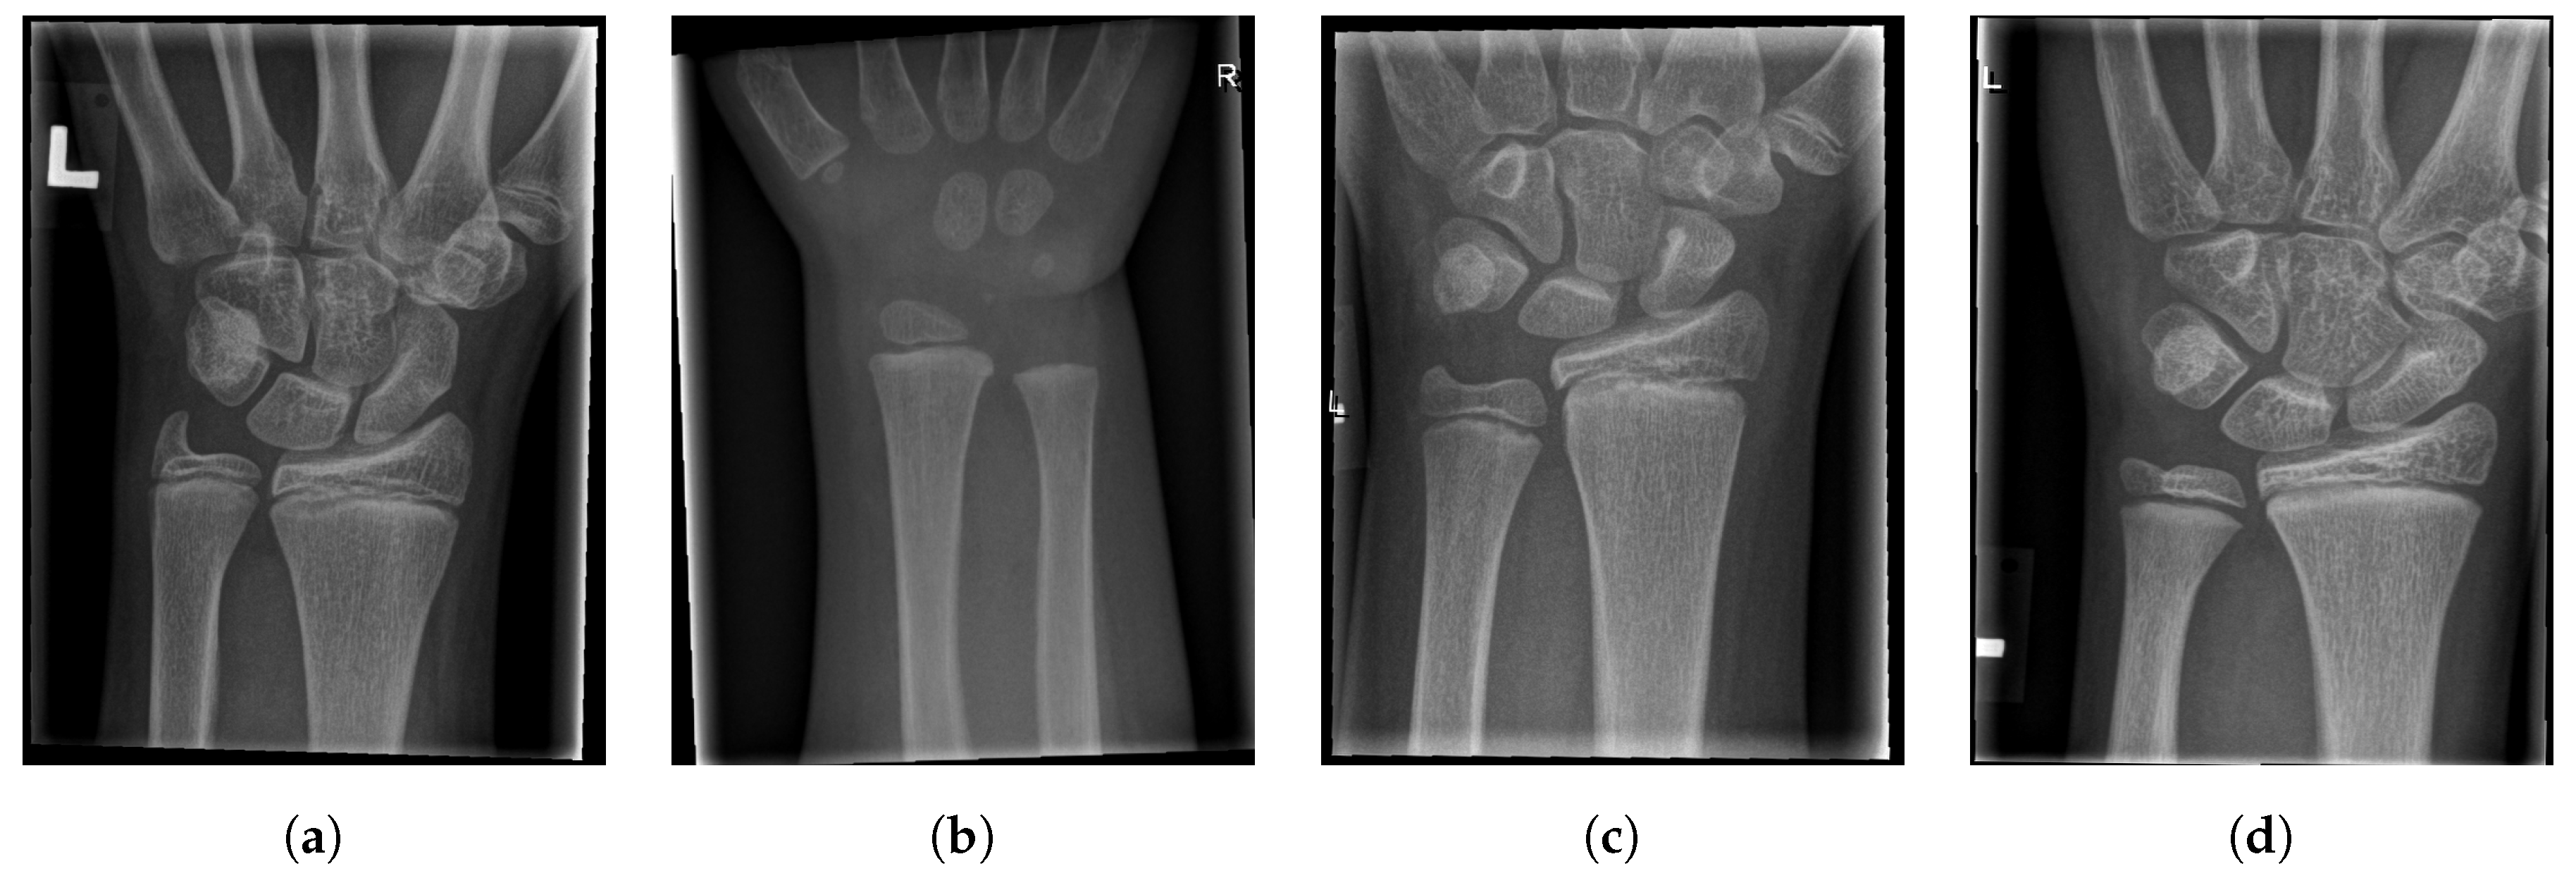

For illustration, four images from each class (TP, TN, FP, and FN) are given in Figure 17, Figure 18, Figure 19 and Figure 20.

Figure 18.

Examples from the true negative (TN) performance metric class.

Examples from the false negative (FN) performance metric class.